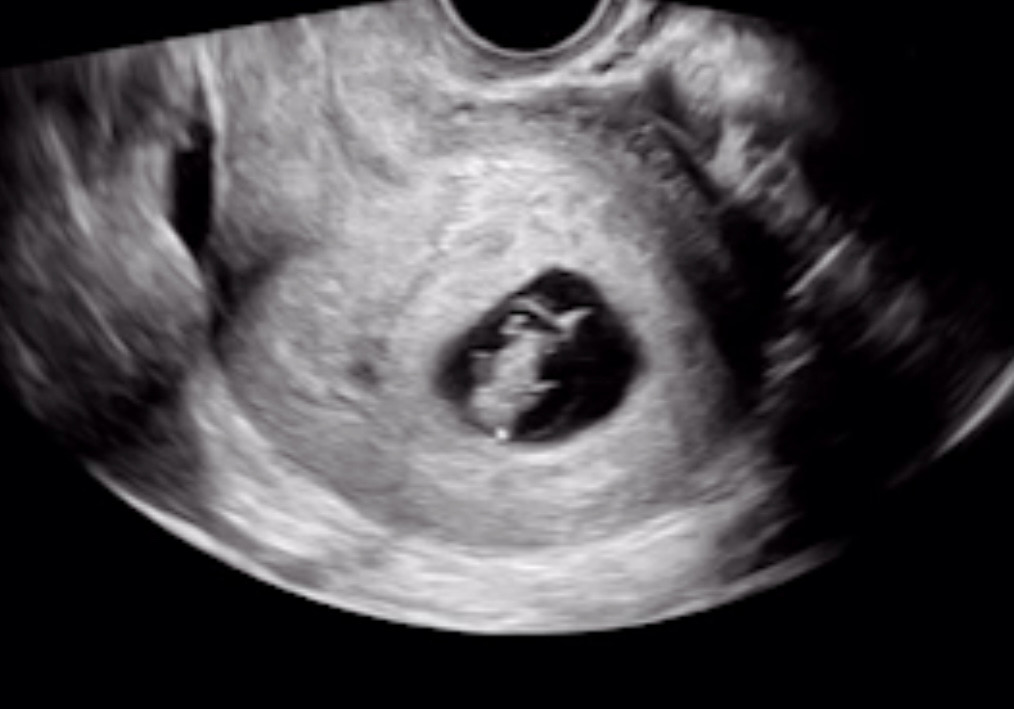

7주차 초음파 사진인데용

귀여운 젤리곰을 기대 했는데 팔다리가 긴건지 꼭 개구리 같네요ㅠㅠㅋㅋㅋ

와 저도 7주 5일때 초음파 팔다리 못봤는데 선명하네요!!?ㅋㅋㅋㅋㅋ

난황도 4주때 이미 보였고 탯줄도 빨리 보이더니 성장이 빠른가봐요 ㅋㅋ

7주 4일인데 탯줄도 빨리 생기고 먹덧이라 엄청 먹는데 아기도 밥 많이 먹고 쑥쑥 크나봐요 ㅋㅋ